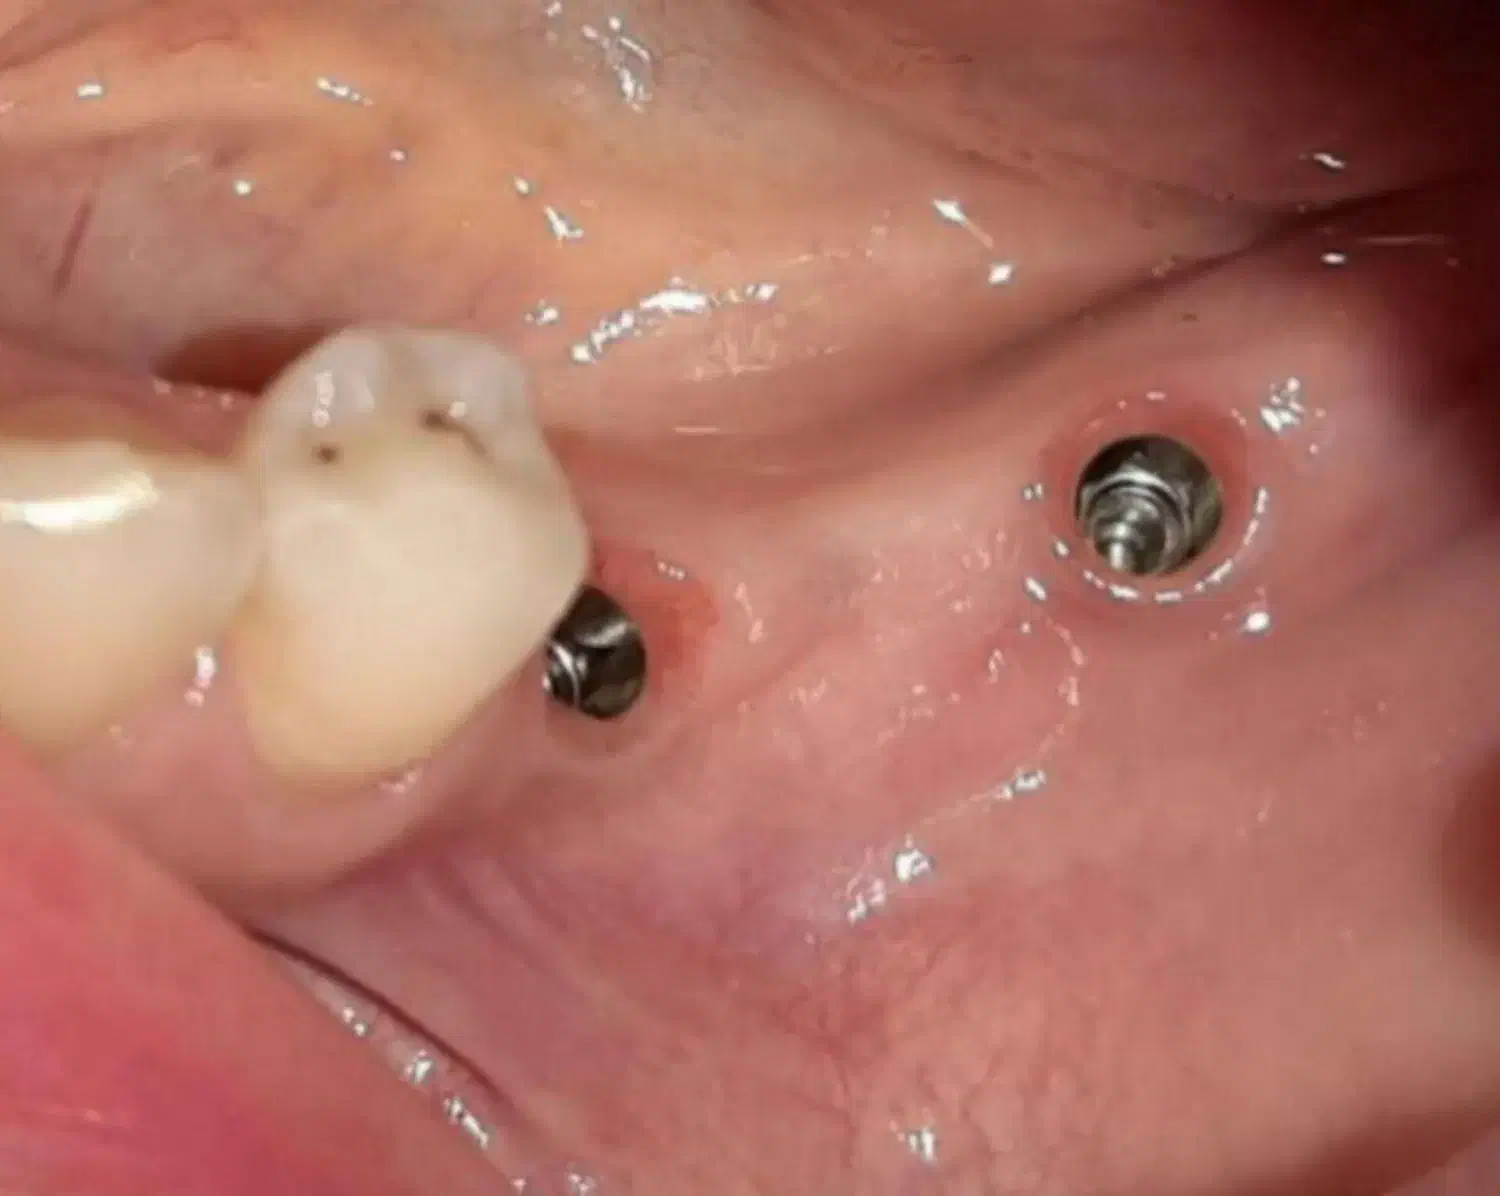

انجام ایمپلنت دندان بدون جراحی با شرایط پرداخت اقساطی مزایای ایمپلنت بدون جراحی: ✅کاهش زمان کاشت دندان ✅کاهش زمان بهبودی ✅کاهش درد، تورم و خونریزی پس از کاشت ✅جلوگیری از تحلیل استخوان مناسب برای افرادی که ترس از جراحی دارند جهت مشاوره و نوبت دهی شماره تماس خود را ارسال نمائید باشما تماس خواهیم گرفت